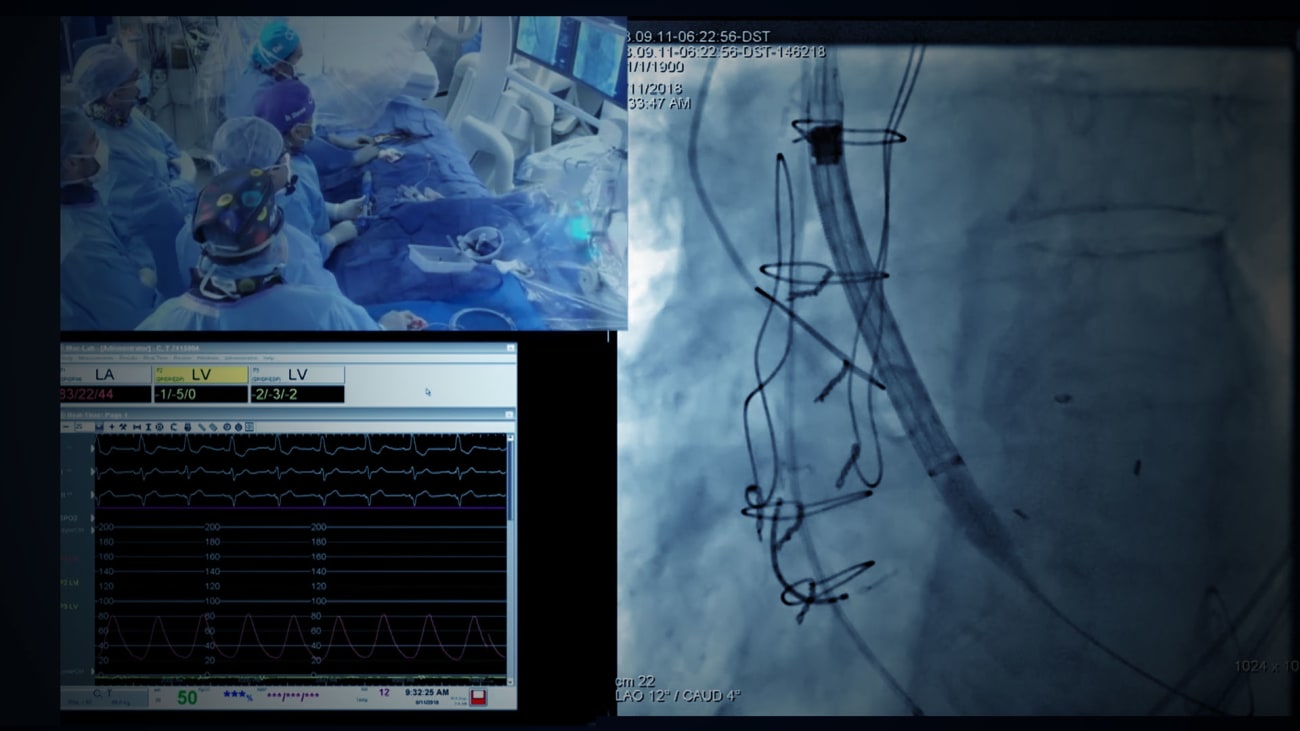

The Cardiac Catheterization Laboratory at The Mount Sinai Hospital has received for the third consecutive year the highest three-star rating, one of the most rigorous and highly respected measures for evaluating the quality of transcatheter aortic valve replacement.